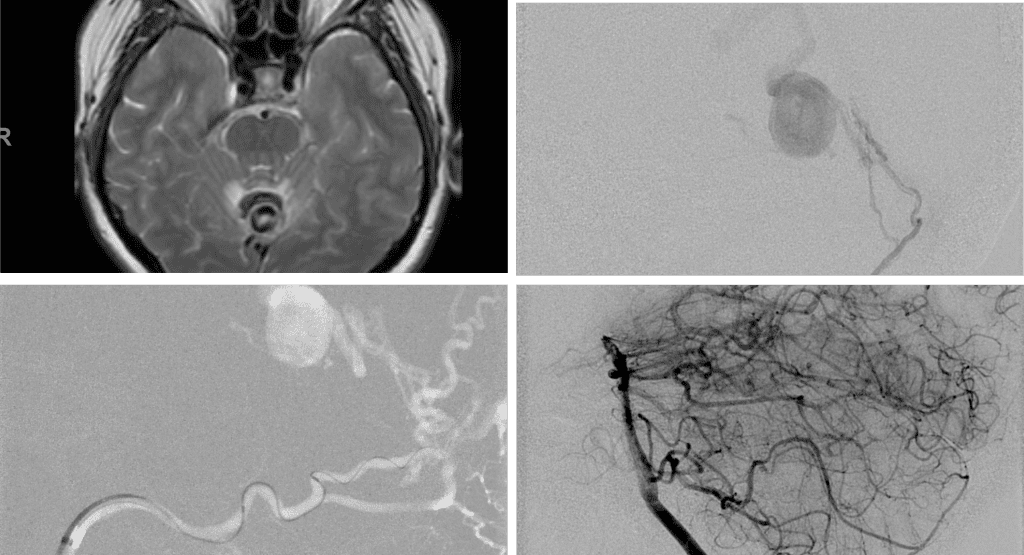

Embolization was successful at immediately reducing the pressure into the Aneurysmal Varix with greater than 90% reduction in A-V shunts. After an intensive period of critical care monitoring and care for her initial brain hemorrhage, she made a near complete recovery with mild intermittent left sided paresthesias and generalized deconditioning. After receiving inpatient and outpatient Acute Rehabilitation, Physical, and Occupational therapy, she completely recovered all of her Activities of Daily Living (ADLs) at 3 months and achieved an modified Rankin Scale (mRS) of 0. On follow-up angiography, small residual low flow A-V shunts were identified and targeted for Gamma Knife Radiosurgery (Figure 5 and 6).

Figure 6. MRI and Catheter Angiograms precisely localize the residual A-V shunts vessels to perform Gamma-Knife Radiosurgery to deliver therapeutic doses to the targets.